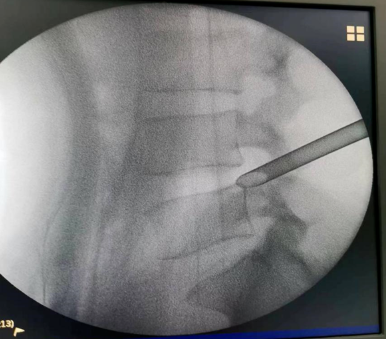

手术经过:术前仔细阅片,精确定位手术靶点部位、规划手术路径、测量通道长度、头尾倾角度。C臂透视定位、局部麻醉、穿刺建立通道、环锯进行关节突成形,连接椎间孔镜系统、椎间盘摘除、神经根管探查减压、侧隐窝减压、彻底检查无卡压后关闭伤口。手术成功,患者术后3天康复出院。

术中穿刺及关节突成形

建立工作通道

连接椎间孔镜系统